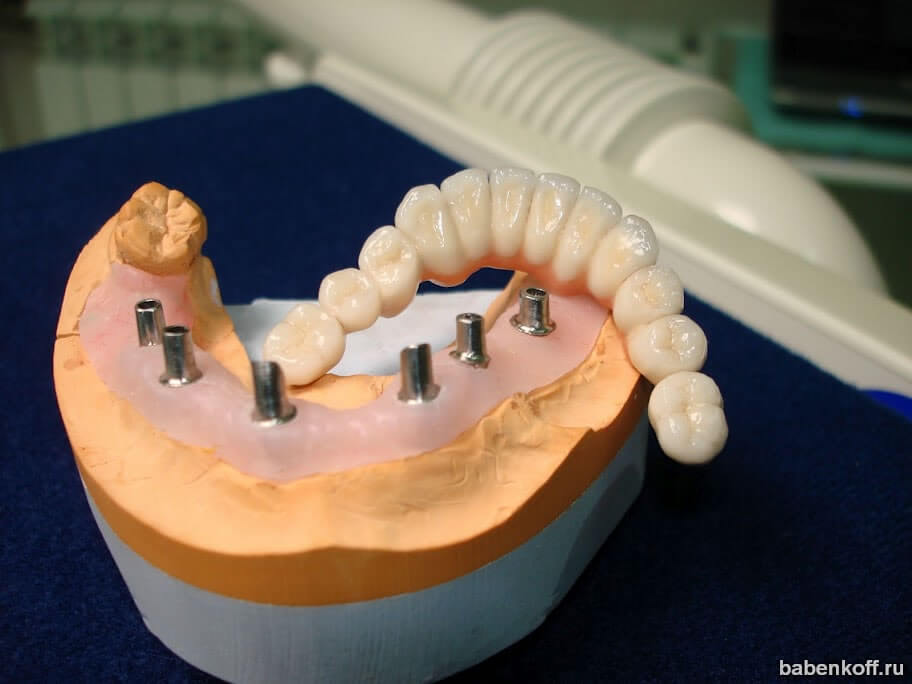

Пошаговое руководство по установке съёмного протеза на импланты